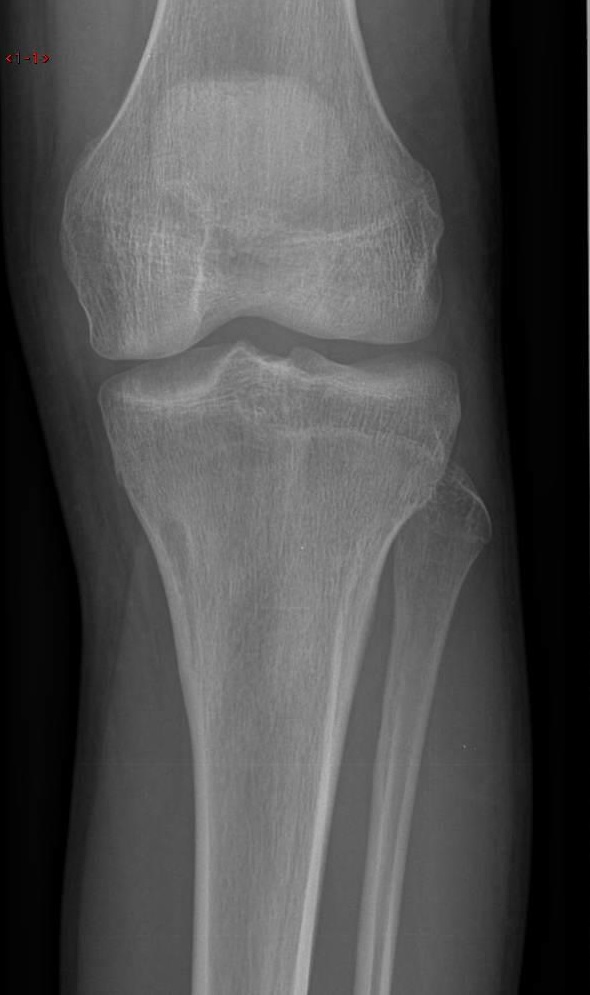

| BONE TUMORS

X-RAY ANALYSIS

• 病人年龄 Patient age

• 骨病变的位置 Skeleton Location

• 边缘 Margins